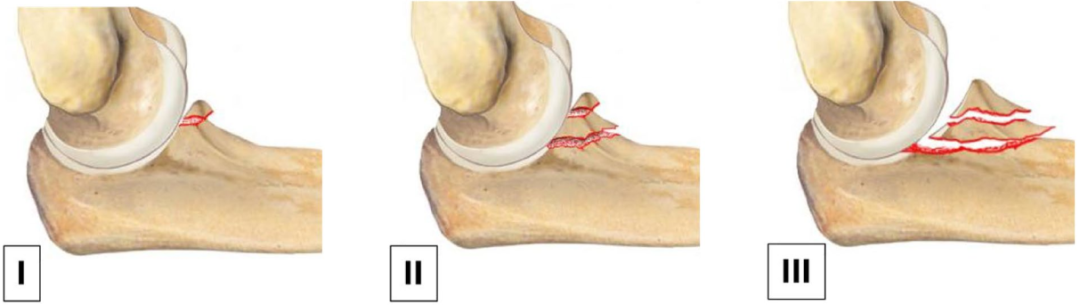

冠状突骨折的分型体系随临床研究的深入不断发展。1989 年,Regan-Morrey首次提出冠状突骨折分型,该分型基于肘关节侧位X线片评估骨折累及冠状突的高度比例,将其分为三型:I型为骨折累及冠状突高度<25%;II型为累及25%~50%;III型为累及>50%。

▲ 正常尺骨轴线与冠突尖、鹰嘴尖连线呈30°角。当骨折累及50%冠突高度时,两线平行。

在II型骨折中,从鹰嘴尖至冠状突骨折基底部的连线与尺骨纵轴基本平行。